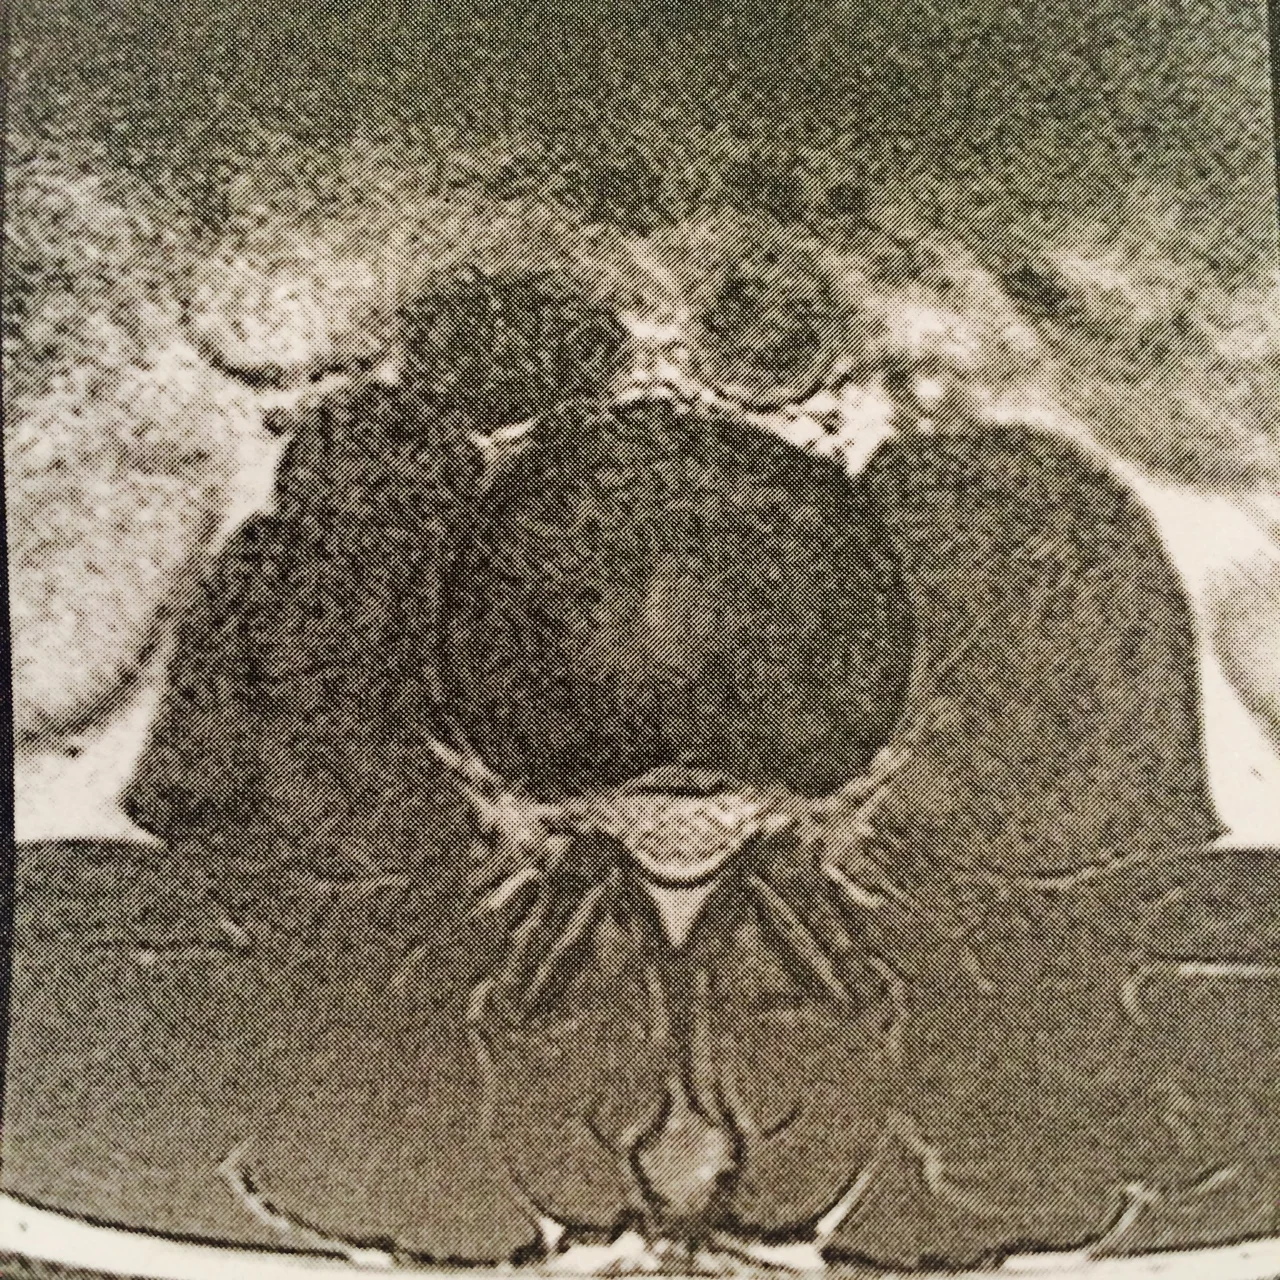

I’ve mentioned this, but back a month ago something went wrong that brought back my back pain. This time it hurt even more and down my back and my legs. Well, it took a month to find out what it probably is - above you can see the higher L2/L3 disc is herniated about 2mm, that’s old news from an accident when I was 21. But the lower herniation in L4/L5 is 3.5mm bulging into my spinal cord. It’s pushing on the nerves that send signals down my legs so that brings out some painful curious uncomfortableness. Like sometimes it feels as though a bear trap with teeth snapped on my leg, sometimes like my knee is being held to a fire, weird phantom pain like that.